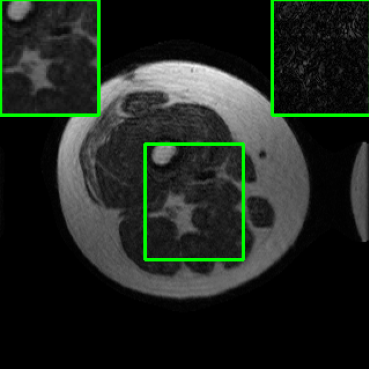

Performance on the Stanford FSE Dataset: We also performed image reconstructions with the Stanford multi-coil FSE dataset, which is a smaller dataset. We used same settings for the networks and training as in Section IV-A. Table III shows that LONDN-MRI significantly outperforms the globally learned MoDL network at both 4x and 8x acceleration. This indicates benefits for the proposed framework for smaller, more diverse datasets. Figs. 7 and 8 display visual comparisons that show the LONDN-MRI scheme recovering sharper features than the globally learned network.

| Ground Truth | Initial | Global | LONDN-MRI | LONDN-MRI | Oracle |

| (1 iteration) | (2 iterations) | ||||

![]() |

| PSNR = dB | PSNR = 22.01 dB | PSNR = 29.02 dB | PSNR = 31.46 dB | PSNR = 31.74 dB | PSNR = 31.87 dB |